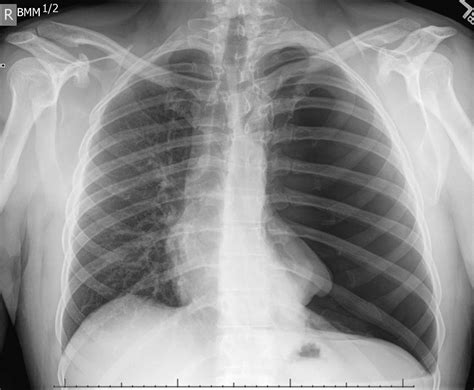

While an X Ray Of Pneumothorax is a valuable diagnostic tool, it does have some limitations. For example, small pneumothoraces may not be visible on a standard chest X-ray, especially in patients with underlying lung diseases. In such cases, additional imaging studies such as a CT scan may be required to provide a more detailed view of the lungs and the pleural space.

Another challenge is the interpretation of X-ray images, which requires a trained eye and a thorough understanding of chest anatomy. Misinterpretation can lead to delayed diagnosis and treatment, potentially compromising patient outcomes.